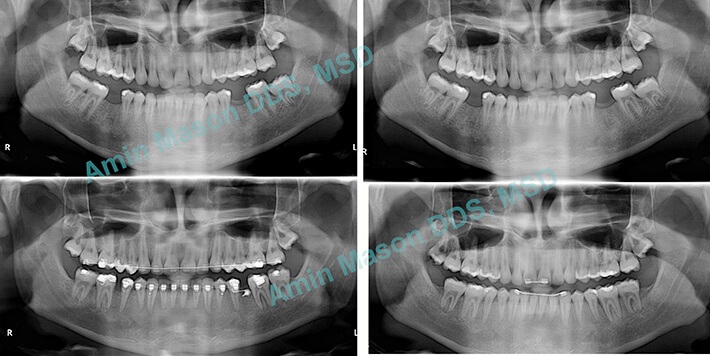

An adult patient with missing mandibular first molars. TADs were used to protract (pull forward) the 2nd and 3rd molars (wisdom teeth). The patient was saved from getting implants for the missing teeth.